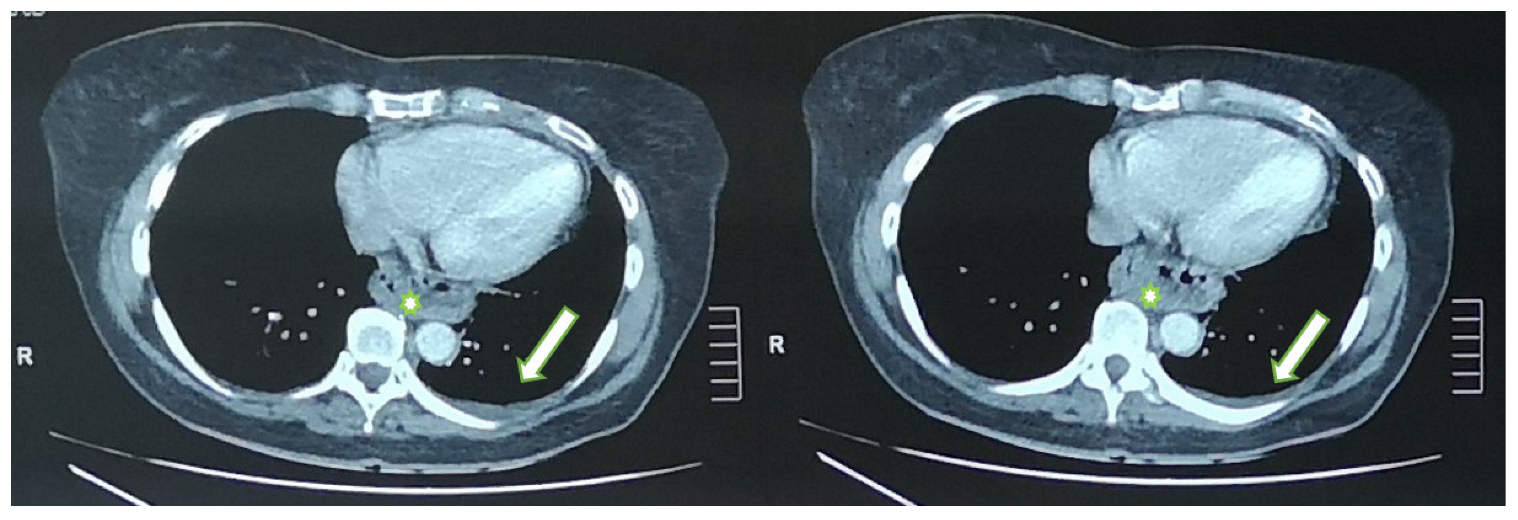

During her stay in the emergency department the 12-lead electrocardiogram showed normal sinus rhythm and the cardiac ultrasound was without any pathological findings. A focused lung ultrasound was conducted without the presence of B-lines, but a small anechoic left pleural effusion was discovered when placing the transducer in the left posterior axillary line at the lower part of the chest (Figure 1). Due to the left sharp “shingles-like” pain and the pleural effusion that was found, an abdomen ultrasound was performed in order to investigate possible abdominal pathology, which was unremarkable. According to the Wells Criteria for Pulmonary Embolism, she was a moderate risk patient for pulmonary embolism. Due to the absence of any other obvious cause of the pleural pain and the pleural effusion, a computed tomography pulmonary angiography (CTPa) was conducted. The CTPa scan was negative for pulmonary embolism, but verified the aforementioned left pleural effusion. The CTPa did not show any other significant findings from the pulmonary parenchyma or the mediastinum, besides a large diaphragmatic hernia already known about (Figure 2).

Figure 2.

Axial CT images show the small left pleural effusion (arrow); diaphragmatic hernia (asterisk).